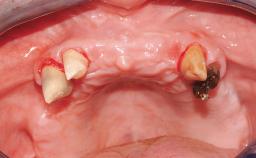

Immediate Loading of Eight Implants in the Maxilla and Six Implants in the Mandible and Final Restoration with Three-Unit and Four-Unit FDPs